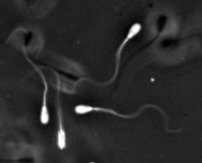

Sperm biology

Specifically, I am interested in studying sperm migration and thereby contributing to the understanding of reasons for infertility. Especially the influence of physical properties, such as surface interactions, charge and viscosity, on successful sperm migration have yet to be investigated. Mimicking in vivo conditions in the lab and investigating sperm kinetics and metabolism under these conditions is my main route for these investigations.